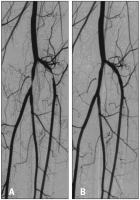

Claudicatio intermittens

Abbildung 1: A. Patient mit ausgeprägter Claudicatio intermittens im linken Unterschenkel und Fuß (Gehstrecke 50 Meter) bei subtotaler Stenose des Truncus tibiofibularis und der proximalen A. tibialis anterior. B. Beschwerdefreiheit nach PTA und Stentimplantation